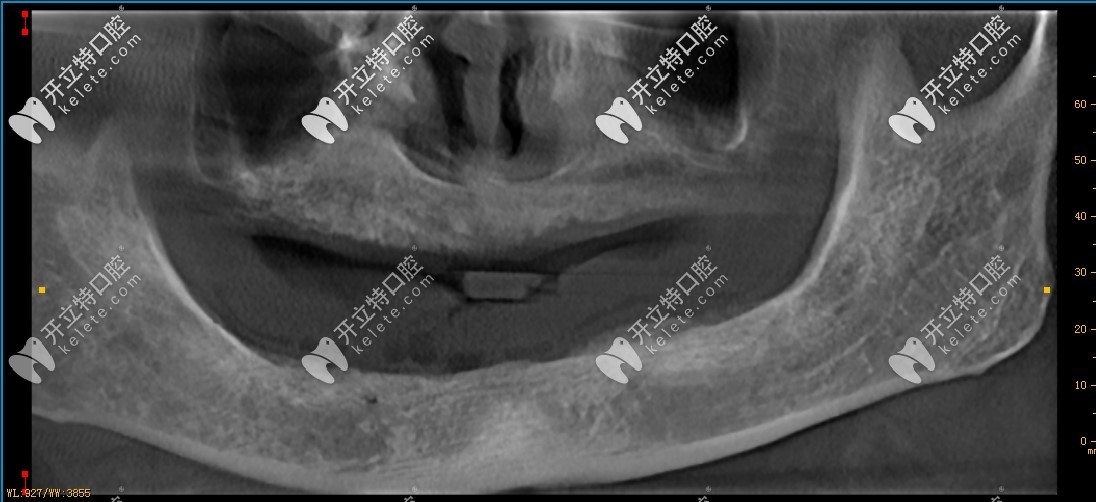

種牙前的牙槽骨

診斷情況:牙槽骨萎縮,需要采用德國生長因子種植技術(shù),采取ALL-on-6即刻種植,上下各6顆植體,再制作連橋冠,共計24顆牙冠。